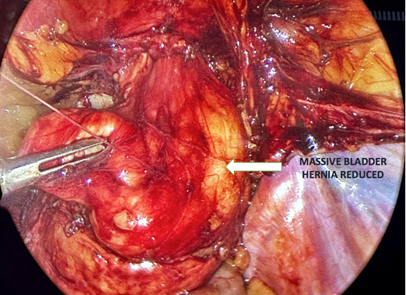

The pneumoperitoneum was induced through an open umbilical incision reducing the umbilical hernia to insert a 12mm trocar. Two more 5mm trocars were inserted 5 cm above the level of the umbilicus over the midclavicular line at each side. The camera was inserted through the 5mm left trocar and the surgeon on the right side working through the umbilical and right-side ports. Dissection began on the left inguinoscrotal hernia, with the patient in the Trendelenburg position, which reduced the small bowel spontaneously (Figure 1 & 2).

Figure 1 Left indirect Hernia with small bowel Incarcerated.